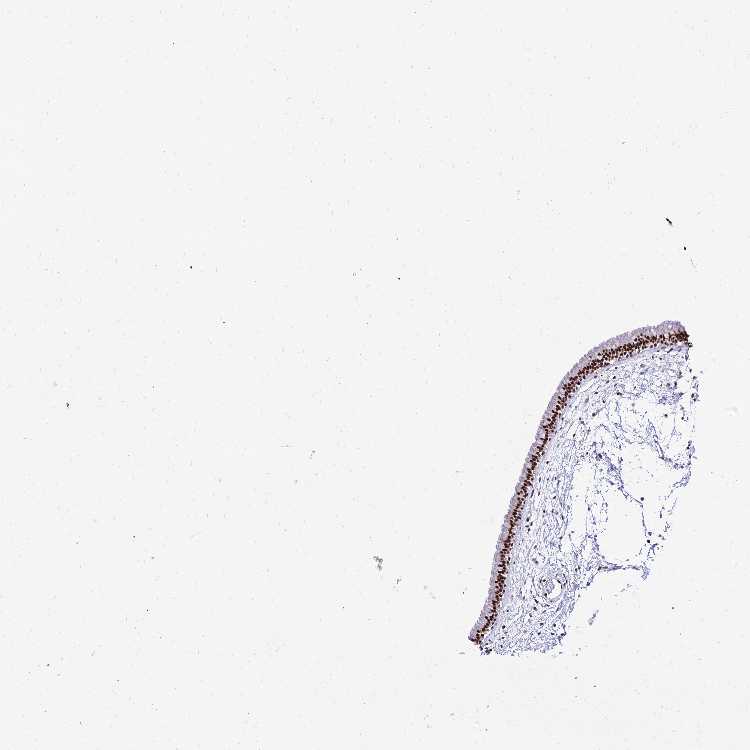

NASOPHARYNX - Antibody stainingi

Antibody staining in the annotated cell types in the current human tissue is reported as not detected, low, medium, or high, based on conventional immunohistochemistry profiling in selected tissues. This score is based on the combination of the staining intensity and fraction of stained cells.

Each image is clickable and will lead to virtual microscopy that enables deeper exploration of all samples and also displays staining intensity scores, fraction scores and subcellular localization as well as patient and tissue information for each sample.

Antibody HPA045268

Respiratory epithelial cells High